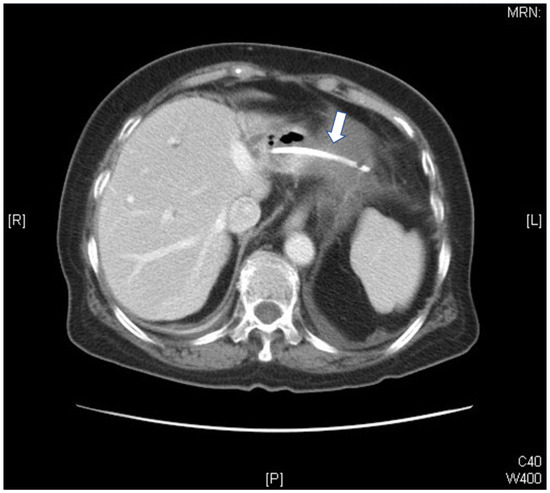

Bacterial Pericarditis Caused by Penetration of a Migrated Biliary Stent from the Lateral Segment of the Liver: A Case Report

2. Case Report